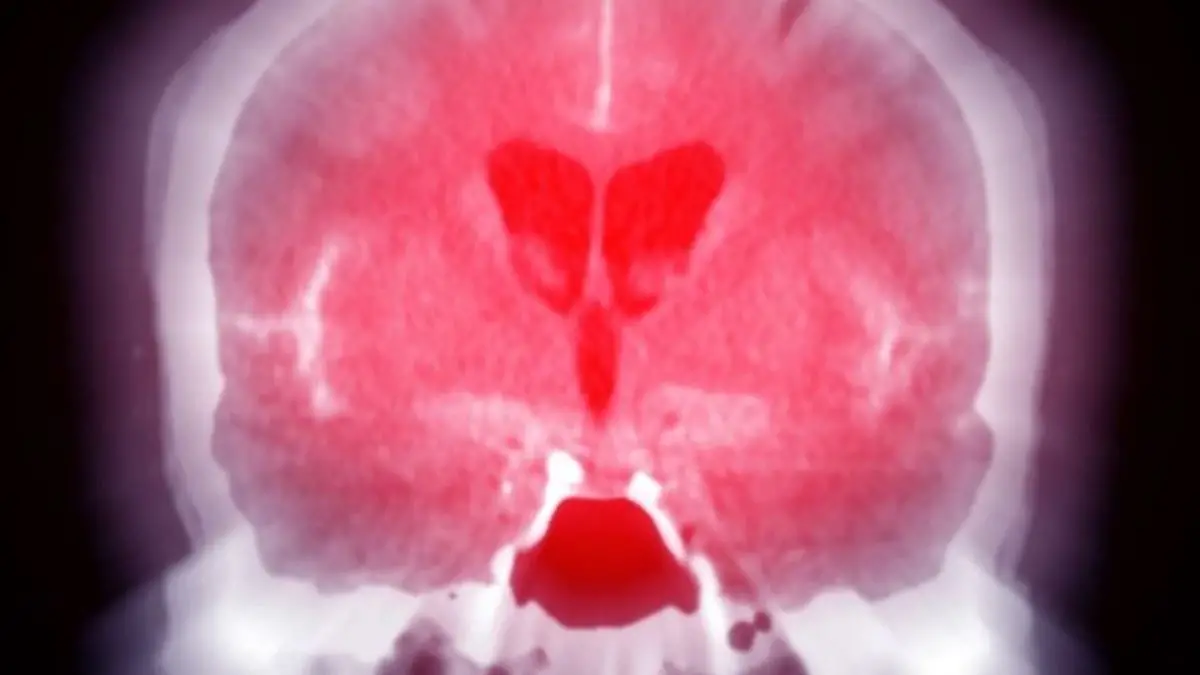

Úgy tűnik, hogy a súlyosabb fejsérülések nemcsak agyi károsodást okozhatnak, hanem az immunrendszer működésére is hatással lehetnek. A folyamat a herpeszvírushoz hasonló lappangó kórokozók újraaktiválódását idézheti elő, ami összefügghet a neurodegeneratív betegségek, többek között az Alzheimer-kór fokozott kockázatával.

A kutatók őssejtekből létrehozott „miniatűr agyakat” tanulmányoztak, és eredményeik alapján arra a következtetésre jutottak, hogy az agyszövet sérülése újraaktiválhatja az immunrendszer által korábban elnyomott herpes simplex vírus 1-et (HSV-1). Az amerikai Tufts Egyetem munkatársa, Dana Cairns és kutatócsoportja azt vizsgálta, hogy egy agyrázkódáshoz hasonlítható fizikai behatás milyen hatással van a mini agymodellekre - írja az origo.hu.

A kísérletek eredményei arra utalnak, hogy egy héttel a fizikai traumát követően a miniatűr agyakban fehérjecsomók jelentek meg, amelyek az Alzheimer-kórhoz hasonló neurodegeneratív betegségek jellemző nyomai. Emellett egyes sejtek gyulladásra utaló károsodást szenvedtek, és jelentősen megnőtt a gyulladást elősegítő immunsejtek mennyisége.